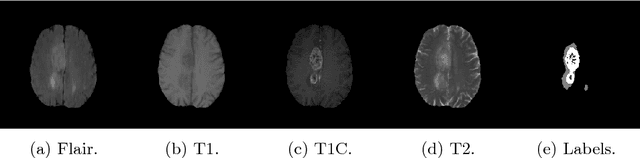

Abstract:In image segmentation, there is often more than one plausible solution for a given input. In medical imaging, for example, experts will often disagree about the exact location of object boundaries. Estimating this inherent uncertainty and predicting multiple plausible hypotheses is of great interest in many applications, yet this ability is lacking in most current deep learning methods. In this paper, we introduce stochastic segmentation networks (SSNs), an efficient probabilistic method for modelling aleatoric uncertainty with any image segmentation network architecture. In contrast to approaches that produce pixel-wise estimates, SSNs model joint distributions over entire label maps and thus can generate multiple spatially coherent hypotheses for a single image. By using a low-rank multivariate normal distribution over the logit space to model the probability of the label map given the image, we obtain a spatially consistent probability distribution that can be efficiently computed by a neural network without any changes to the underlying architecture. We tested our method on the segmentation of real-world medical data, including lung nodules in 2D CT and brain tumours in 3D multimodal MRI scans. SSNs outperform state-of-the-art for modelling correlated uncertainty in ambiguous images while being much simpler, more flexible, and more efficient.